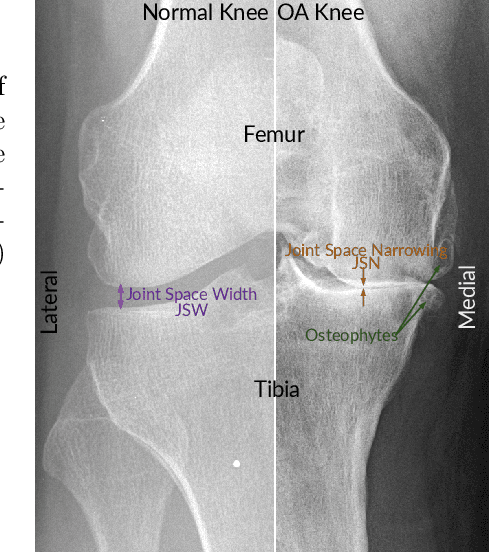

Knee osteoarthritis (OA) is very common progressive and degenerative musculoskeletal disease worldwide creates a heavy burden on patients with reduced quality of life and also on society due to financial impact. Therefore, any attempt to reduce the burden of the disease could help both patients and society. In this study, we propose a fully automated novel method, based on combination of joint shape and convolutional neural network (CNN) based bone texture features, to distinguish between the knee radiographs with and without radiographic osteoarthritis. Moreover, we report the first attempt at describing the bone texture using CNN. Knee radiographs from Osteoarthritis Initiative (OAI) and Multicenter Osteoarthritis (MOST) studies were used in the experiments. Our models were trained on 8953 knee radiographs from OAI and evaluated on 3445 knee radiographs from MOST. Our results demonstrate that fusing the proposed shape and texture parameters achieves the state-of-the art performance in radiographic OA detection yielding area under the ROC curve (AUC) of 95.21%